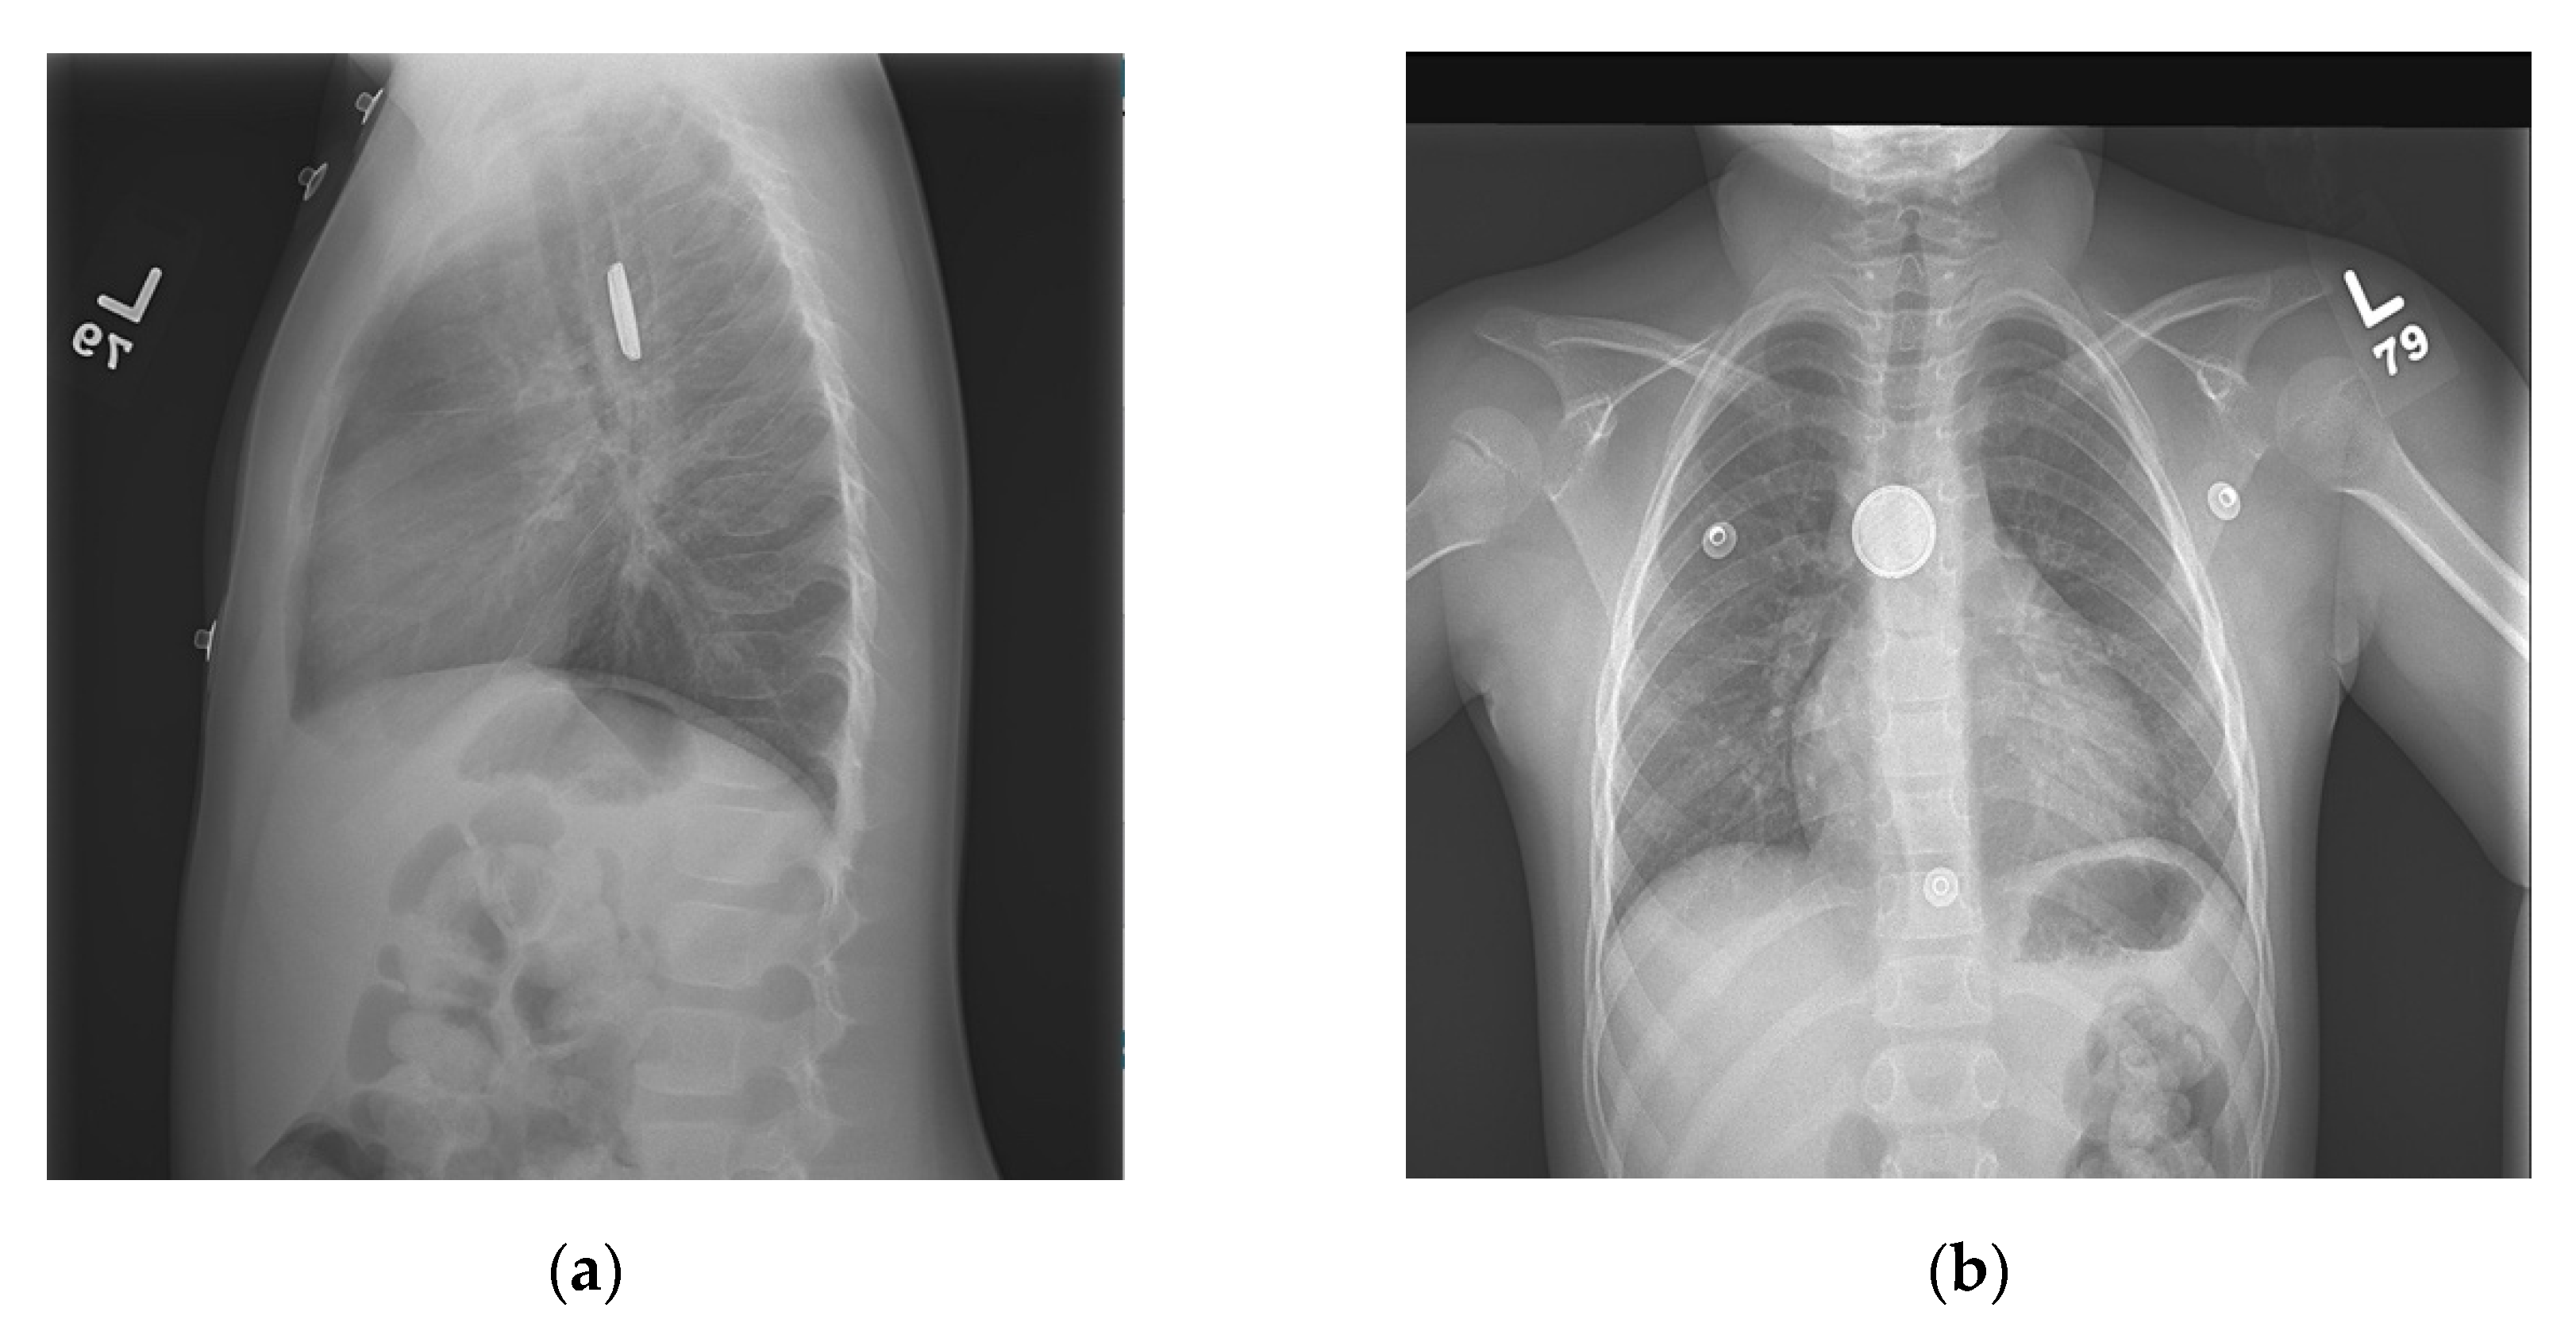

Button Battery Ingestion X Ray . A halo sign or double ring sign can be seen which eludes towards the foreign. Suspect a button battery ingestion in every presumed coin or other foreign body ingestion. A foreign body is seen at the level of the cricopharyngeus. In case of multiple coin ingestion or unclear history from parent/patient, anteroposterior (ap) and lateral radiographs may both help in differentiating coins from button batteries. A metallic foreign body projects over the right upper abdomen. If there is a known bb ingestion, x‐ray should be obtained in all patients except. The evaluation and management of button and cylindrical battery ingestion will be presented here.

In case of multiple coin ingestion or unclear history from parent/patient, anteroposterior (ap) and lateral radiographs may both help in differentiating coins from button batteries. If there is a known bb ingestion, x‐ray should be obtained in all patients except. A halo sign or double ring sign can be seen which eludes towards the foreign. A foreign body is seen at the level of the cricopharyngeus. The evaluation and management of button and cylindrical battery ingestion will be presented here. Suspect a button battery ingestion in every presumed coin or other foreign body ingestion. A metallic foreign body projects over the right upper abdomen.

Button Battery Ingestion X Ray Suspect a button battery ingestion in every presumed coin or other foreign body ingestion. If there is a known bb ingestion, x‐ray should be obtained in all patients except. The evaluation and management of button and cylindrical battery ingestion will be presented here. A metallic foreign body projects over the right upper abdomen. A halo sign or double ring sign can be seen which eludes towards the foreign. A foreign body is seen at the level of the cricopharyngeus. Suspect a button battery ingestion in every presumed coin or other foreign body ingestion. In case of multiple coin ingestion or unclear history from parent/patient, anteroposterior (ap) and lateral radiographs may both help in differentiating coins from button batteries.